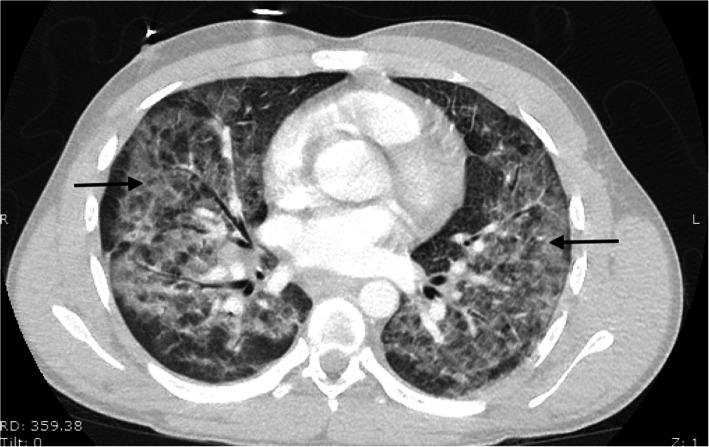

Laboratory studies revealed leukocytosis of 17.0 × 109/L with 93% neutrophils and an elevated lactic acid of 1.9 mmol/L. The findings of the patient’s chemistry panel were unremarkable. His urine drug screen result was positive for cannabinoids and benzodiazepines. His erythrocyte sedimentation rate was slightly elevated at 63 mm/hour. His human immunodeficiency virus and hepatitis B and C virus test results were negative. A viral panel was obtained, which showed positive results for rhinovirus and enterovirus, but otherwise negative findings were reported. This patient’s hospitalization occurred before the coronavirus disease 2019 (COVID-19) pandemic; therefore, no COVID-19 testing was available at the time. He had negative test results for antineutrophil antibodies, cytoplasmic and perinuclear antineutrophil cytoplasmic antibodies, and myeloperoxidase. His echocardiogram demonstrated a left ventricular ejection fraction of 64%; otherwise, he had no effusion, no vegetation, or other acute findings. A plain chest x-ray (CXR) (Fig. 2) demonstrated diffuse central predominant interstitial opacities. A computed tomographic (CT) angiogram of the chest was then obtained (Figs. 3 and 4), which confirmed diffuse bilateral interstitial infiltrates, with no evidence of vascular injury or pulmonary embolism.